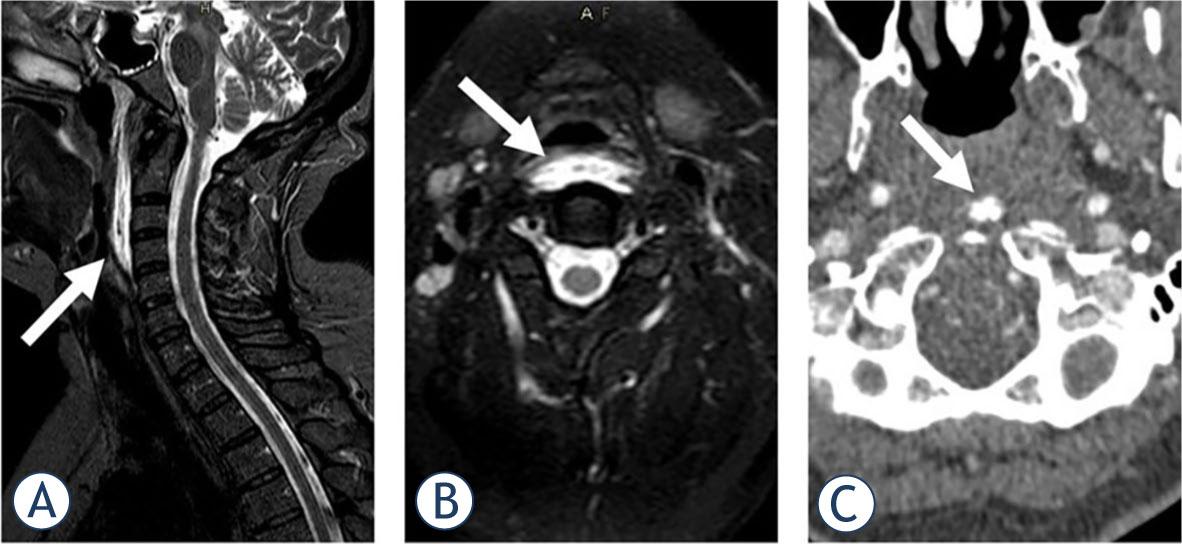

Radiological clues for differential diagnosis

| MR | May suggest calcifications LCM oedema | +Diffusion restriction (pus) | (Superior contrast resolution) |